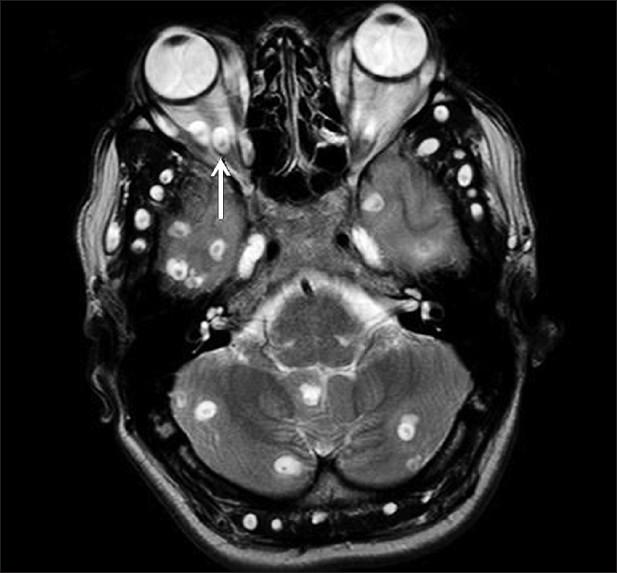

In this study, we present a case of disseminated cysticercosis involving the brain, orbit, myocardium, muscle, subcutaneous tissues, pancreas, and spleen. Imaging studies are described with emphasis on pancreatic and splenic involvement which is a rare manifestation of a rather common disease and has been radiologically demonstrated only once previously. Although the involvement of the pancreas by parasites leading to pancreatitis has been described previously, in our case there was no clinical or biochemical evidence of pancreatitis due to infection by cysticerci.

在本研究中,我们报告了一例播散性囊尾蚴病病例,累及脑、眼眶、心肌、肌肉、皮下组织、胰腺和脾脏。描述了影像学检查,重点是胰腺和脾脏受累情况,这是一种常见疾病的罕见表现,此前仅在放射学上有过一次报道。虽然之前曾描述过寄生虫累及胰腺导致胰腺炎的情况,但在我们的病例中,没有临床或生化证据表明是由囊尾蚴感染引起的胰腺炎。